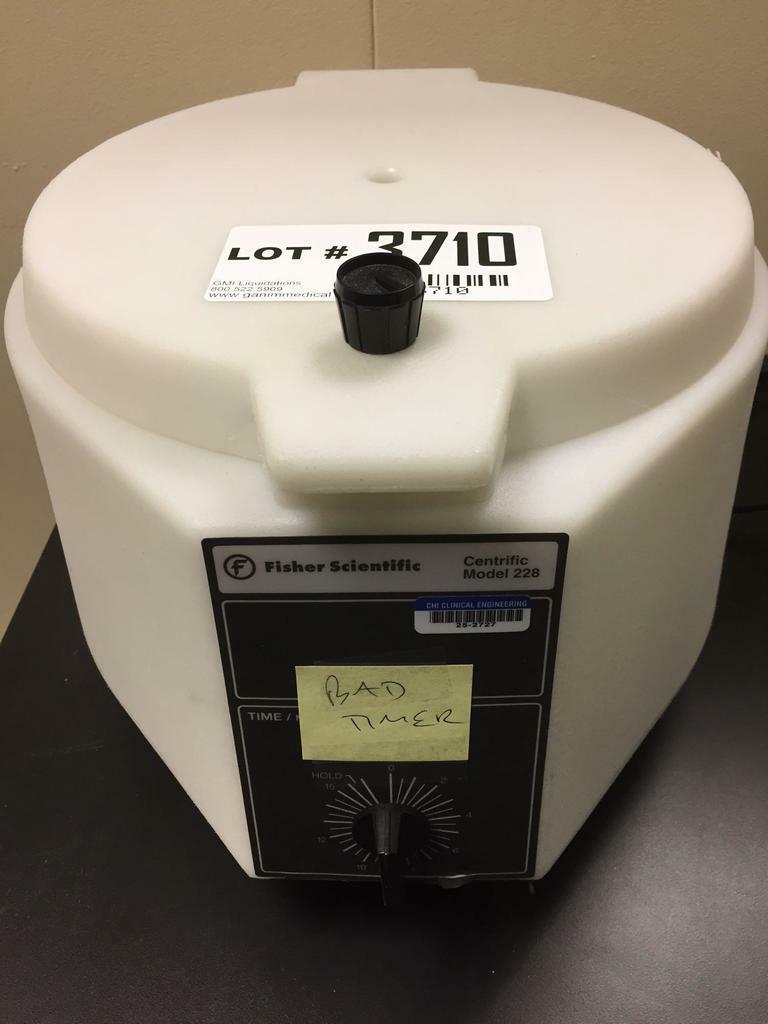

DIAGNOSTIC ULTRASOUND MACHINES FOR SALE

LINVATEC Advantage D9824 Shaver Handpiece

Sale price$ 1,474.36